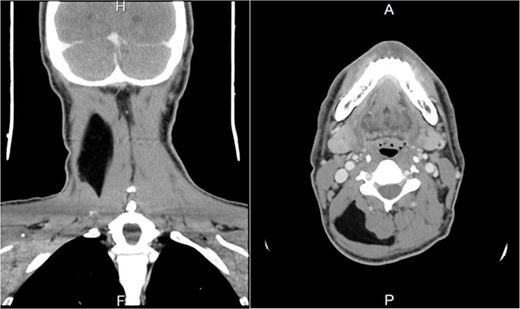

A contrast-enhanced computed tomography (CT) scan revealed a right posterior neck lipoma between the trapezius and splenius capitis muscles. No associated enhancing solid nodules or cervical lymphadenopathy were observed. The radiological findings were consistent with those of benign lipomas (Fig. 1).

Preoperative contrast-enhanced CT image. (A) A coronal section shows a right hypodense mass between the trapezius and splenius capitis muscle. (B) Axial section shows a right hypodense mass between the trapezius and splenius capitis muscles.